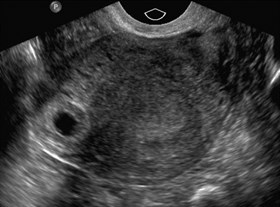

Ultrasonographic Appearance Of Cornual Ectopic Pregnancy. | Download

Ultrasonographic appearance of cornual ectopic pregnancy. | Download www.researchgate.net

Emergency Ultrasound Identification Of A Cornual Ectopic Pregnancy

Emergency Ultrasound Identification of a Cornual Ectopic Pregnancy westjem.com

cornual pregnancy ectopic ultrasound emergency